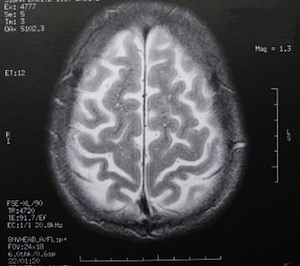

Sie sind hier: Startseite Nachrichten Gesundheit Wissenschaftler: In der Pubertät sterben Milliarden Gehirnzellen ab Das menschliche Gehirn verfügt über enorme "Rechenpower". Bild: pixelio.de/Dieter Schütz

Das menschliche Gehirn verfügt über enorme "Rechenpower". Bild: pixelio.de/Dieter Schütz